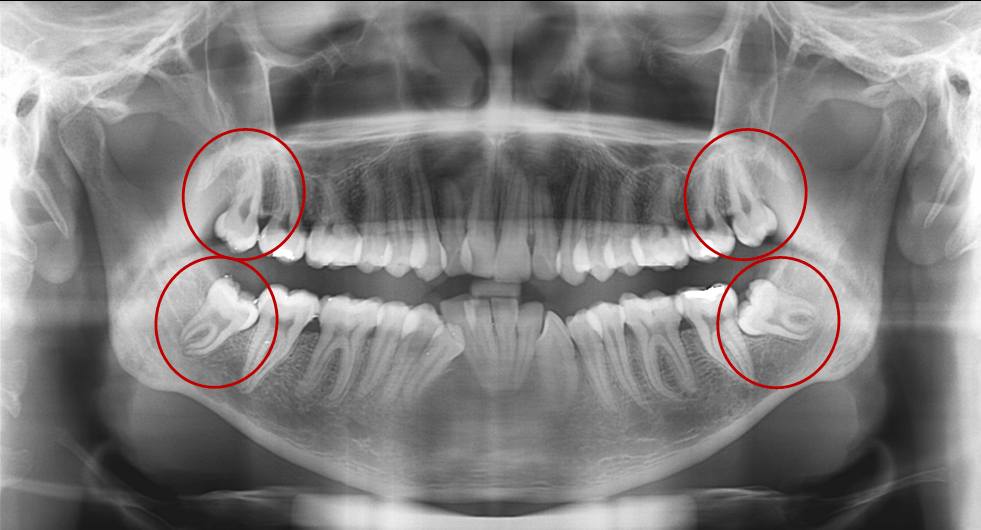

Важно понимать, что решение об удалении зуба мудрости принимается не только из-за боли или воспаления. Иногда зуб может находиться в «ретинированном» положении — то есть оставаться внутри десны или расти под углом. В таких случаях он не виден при обычном осмотре, и выявить проблему можно только с помощью рентгенографии. Именно поэтому регулярные профилактические визиты к стоматологу позволяют выявить скрытые риски и своевременно провести лечение.

- Рентгенография для оценки положения зуба

- Осмотр полости рта для выявления потенциальных осложнений